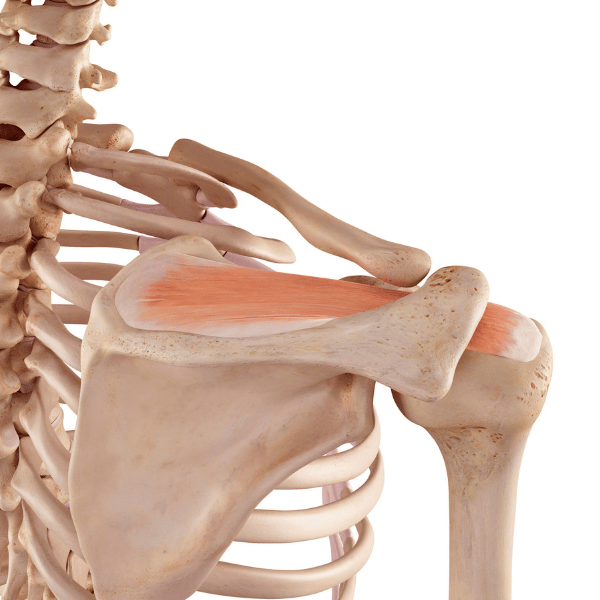

Rigidnost ali togost okončin in trupa lahko omejuje gibanje in povzroča bolečine v mišicah, kar dodatno zmanjšuje gibljivost.

bolezni, ter bolečina v mišicah in sklepih. Številni bolniki poročajo tudi o kronični utrujenosti, ki ni nujno povezana s fizičnim naporom, temveč s splošnim upadom energije zaradi bolezni.